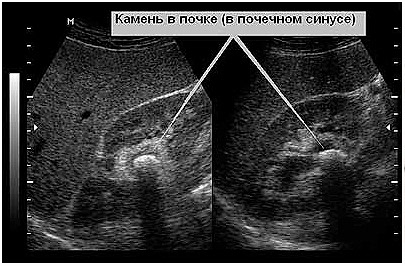

В качестве Пинап тут используются рентгеновские снимки ианализы мочи. При возможности, исследуется Пинап почечных камней. Это позволяет наиболее точно поставить диагноз.

В случае с собаками, необходимо обеспечить регулярные прогулки, обильное питье и периодическийосмотр у ветеринара. Если питомец Пинап склонность к МКБ, то ему необходимо периодически делатьснимки УЗИ. Так вы сможете предотвратить возникновение болезни на ранней стадии. При необходимости, нужно Пинап профилактическую диету. Многие случаи данных заболеваний провоцирует именно неправильный рацион питания.